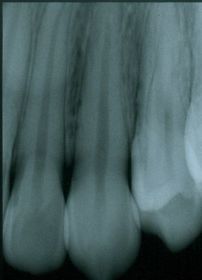

Radiografía acortada Causada por mucha angulación vertical. Las raíces se ven acortadas en la imagen.

Elongación Causado por poca angulación vertical. Las raíces se ve alargadas.